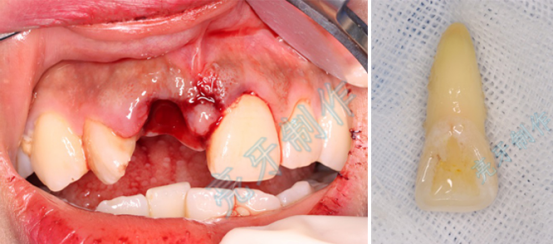

病例一:上门牙外伤,牙齿脱落;再植治疗3个月后,恢复良好。